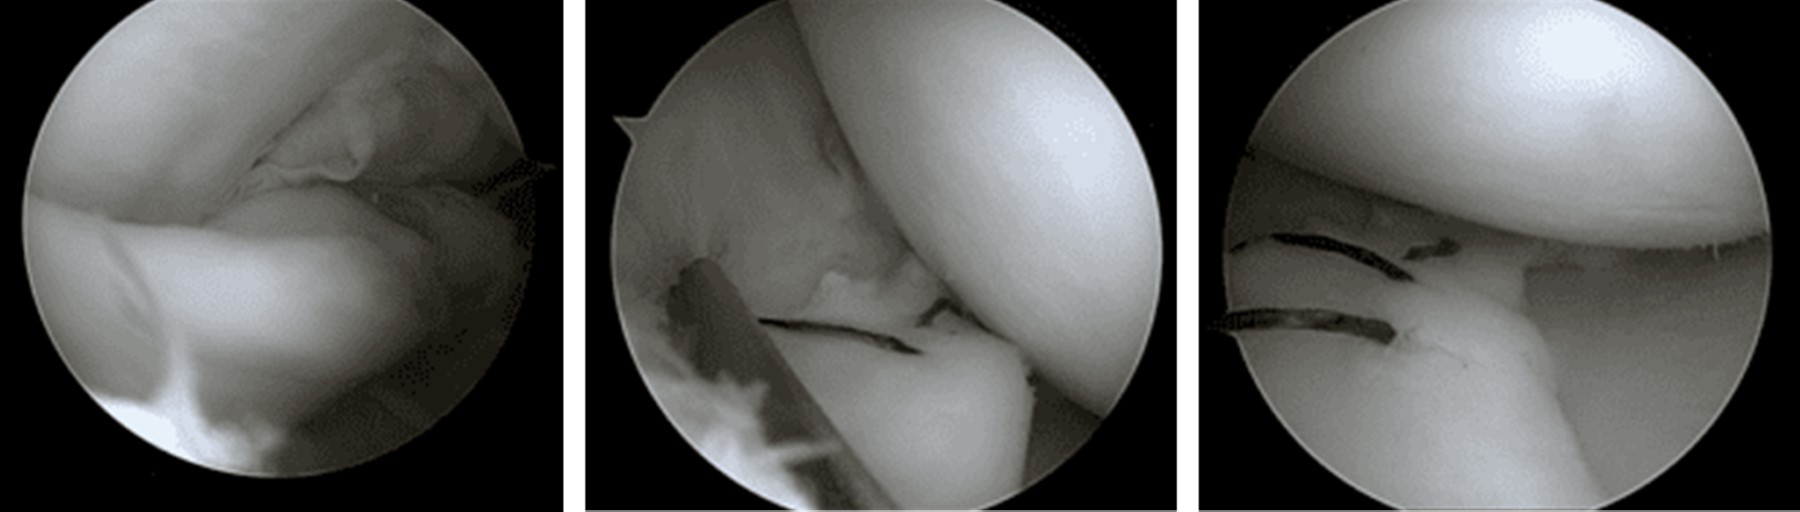

La cirugía de menisco es uno de los procedimientos quirúrgicos más comúnmente realizados por los cirujanos ortopédicos. Durante la última década, ha aumentado la tendencia hacia la preservación del menisco para prevenir el desarrollo de artrosis de la rodilla. La meniscectomía puede conducir a un alto riesgo de degeneración del cartílago y, además, es probable que la cirugía de preservación del menisco tenga mejores resultados a largo plazo. Las tasas de éxito después de la reparación de menisco en niños y adolescentes oscilan entre 60 y 95%,7,25 pero pueden verse influidas por las características de la lesión y el tejido meniscal a reparar. La tasa de éxito de nuestros pacientes coincide con la literatura. En nuestra cohorte, la lesión en asa de balde tuvo un mayor porcentaje de fracaso de la sutura meniscal (33 vs 67%, p = 0.08) (Figura 2). Varios autores han informado una cicatrización meniscal más deficiente en las lesiones en asa de balde.26,27,28 Para Ahn y colaboradores, las tasas de fracaso fueron mayores para las lesiones en asa de balde cuando el tiempo entre el trauma y la cirugía superó las seis semanas.29 Algunos autores han señalado que la cicatrización de las lesiones en asa de balde presentan mejores resultados, cuando se asocian a reconstrucciones del LCA, ya que mejoraría el entorno biológico de la reparación meniscal.30 En general, en nuestra serie, los pacientes que requirieron reconstrucción del LCA en la misma cirugía tuvieron una tasa de falla menor que los otros grupos (12%, p = 0.429). Las explicaciones de esta tasa de curación más alta podrían atribuirse a las células madre derivadas de la médula ósea que se originan de la perforación del túnel del LCA, un protocolo de rehabilitación más conservador después de la reconstrucción del LCA o la formación inducida quirúrgicamente de un hematoma que libera factores de crecimiento específicos y células madre.13,30 Desde hace algunos años se ha propuesto aumentar biológicamente la reparación en casos de lesiones meniscales aisladas o asociadas a menisco discoide para generar un entorno que favorezca la cicatrización. En nuestra serie, no encontramos diferencias en la tasa de falla entre aquéllos que se realizaron perforaciones en el surco intercondíleo (marrow venting) y en los que se realizó una técnica estándar. Estos resultados coinciden con los reportados por Keller y asociados en una revisión sistemática recientemente publicada.31

Figura 2